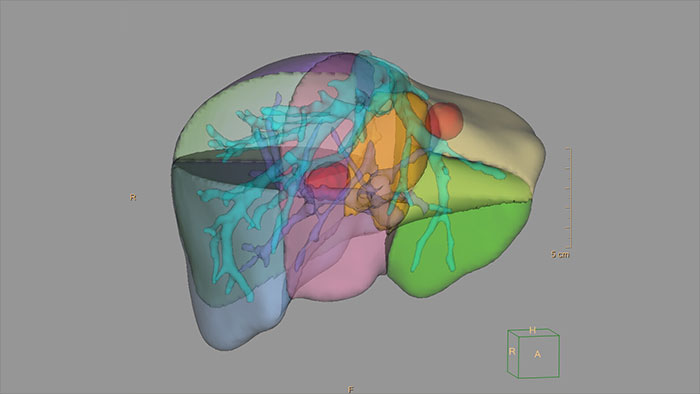

Streamlined modeling workflow optimized for 3D printing

IntelliSpace Portal features a dedicated 3D Modeling application for creating and exporting 3D models. An integrated segmentation environment incorporates IntelliSpace Portal’s segmentation tools in one place designed to simplify workflow.

Benefits

- 3D Modeling batches files for easy export in standard formats (i.e. STL) and also in 3D PDF that can be used for communication in department. - A variety of export options help streamline the transference of your file to a printing service, or for hospital internal use.

*In the USA, 3D models are not intended to be used for diagnostic use.